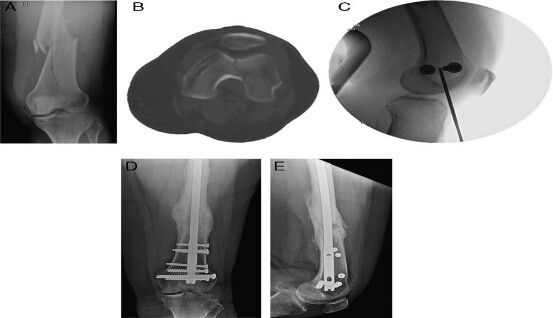

骨質(zhì)疏松性股骨遠(yuǎn)端骨折鋼板內(nèi)固定的一個(gè)主要問(wèn)題是偏心承擔(dān)載荷的問(wèn)題,這會(huì)限制老年患者的負(fù)重。因此,可以分擔(dān)載荷、允許早期負(fù)重的交鎖髓內(nèi)釘被認(rèn)為是骨質(zhì)疏松性股骨遠(yuǎn)端骨折的良好替代固定裝置(圖 2)。此外,交鎖髓內(nèi)釘屬于一種微創(chuàng)手術(shù)方式具有諸多優(yōu)勢(shì),而且也不用擔(dān)心鋼板的突出問(wèn)題。

圖 2 為 63 歲女性下坡時(shí)不慎摔倒導(dǎo)致股骨遠(yuǎn)端骨折。 A 為受傷時(shí)前后位 X 線;B 為關(guān)節(jié)面的軸向 CT 顯示無(wú)移位的股骨髁劈裂骨折;C 為術(shù)中透視顯示逆行髓內(nèi)釘?shù)娜脶旤c(diǎn)位于兩枚固定股骨髁劈裂骨折的骨塊拉力螺釘之間;D 和 E 為術(shù)后 1 年隨訪影像顯示骨折愈合